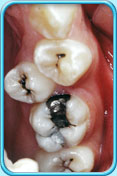

核心提示:蛀坏的部分会发出异味,导致口臭,直接影响日常的社交生活。 蛀牙可能会带来持续不断的疼痛,影响食欲、学业、工作、睡眠,甚至身体健康。 蛀牙严重时,细菌甚至可能从牙髓经牙根部分扩散到附近的牙周组织,引致发炎或脓肿 。   若牙齿受到严重破坏,进行牙髓治疗可能亦无法把牙齿修复,这样,就必须拨除牙齿。拨除牙齿後,附近的牙齿就会向

蛀坏的部分会发出异味,导致口臭,直接影响日常的社交生活。

蛀牙可能会带来持续不断的疼痛,影响食欲、学业、工作、睡眠,甚至身体健康。

蛀牙严重时,细菌甚至可能从牙髓经牙根部分扩散到附近的牙周组织,引致发炎或脓肿 。

若牙齿受到严重破坏,进行牙髓治疗可能亦无法把牙齿修复,这样,就必须拨除牙齿。拨除牙齿後,附近的牙齿就会向空位移位,造成牙齿移位。